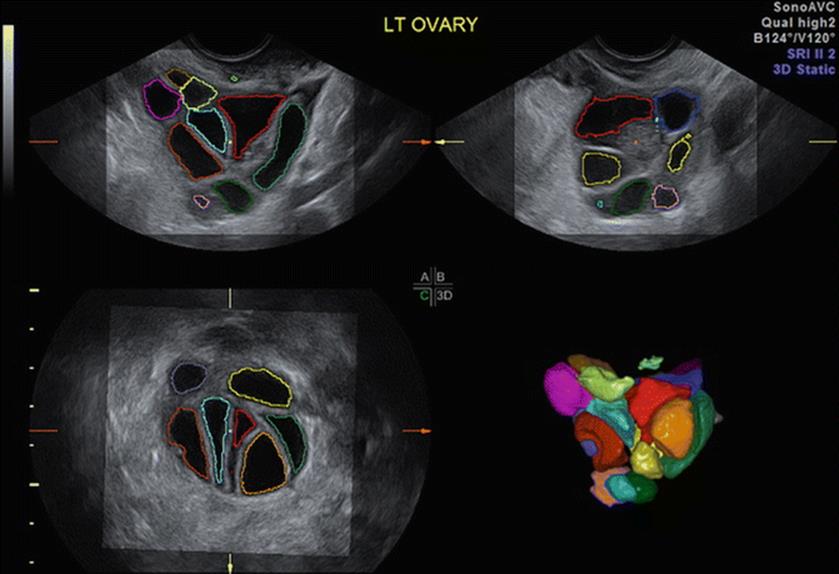

The AFC can be evaluated either using the 2-dimensional (2D), 3-dimensional (3D), or 4-dimensional (4D) ultrasonography (USG) (Sono AVC – hypoechoic aspect of the ultrasound display is inverted to demonstrate fluid-filled areas within the 3D dataset). Sono AVC (Fig. 2.4) is the best model for predicting the number of oocytes retrieved with a retrieval rate of 60 %. AFC is a good predictor of response but not of pregnancy. The optimum cut-off value of AFC for poor response is ≤10 but the post-test probability was reported to be the highest at cut-off levels of <8 [1].

Fig. 2.4

Sono AVC

Tridimensional Automated USG for Monitoring Controlled Ovarian Stimulation Cycles

Two-dimensional USG is difficult and less reliable in the presence of numerous follicles of different sizes during COS and is also relatively arbitrary. Accurate assessment of follicular size is required for timing and oocyte collection as significantly less mature oocytes are recovered from follicles with a mean diameter of <15 mm. Three-dimensional ultrasonography-based automated volume count (SonoAVC) can individually identify and quantify the size of any hypoechoic region within the 3D data sets (Fig. 2.26), providing an automatic estimation of their absolute dimension and volume. It estimates the volume of follicle to within ±0.5 cm3. This enables the quantification of an unlimited number of volumes that arise in a COS cycle, as it eliminates the possibility of measuring the same follicle more than once. Thus, Sono AVC is a quicker and more reliable method of measuring follicles in a COS cycle, but its effect on the pregnancy rate has not yet been studied. The number of the mature oocytes, fertilized oocytes, and clinical the pregnancy rates (42 % vs. 43 %) were similar with both 2D ultrasound and Sono AVC methods [49].

Fig. 2.26

(a, b) SonoAVC for follicular monitoring

Three-dimensional ultrasound with Sono AVC significantly improves the interobserver reliability of antral follicle counts and allows quicker assessment of follicle size and number, making it an important tool in the assessment of ovarian reserve.